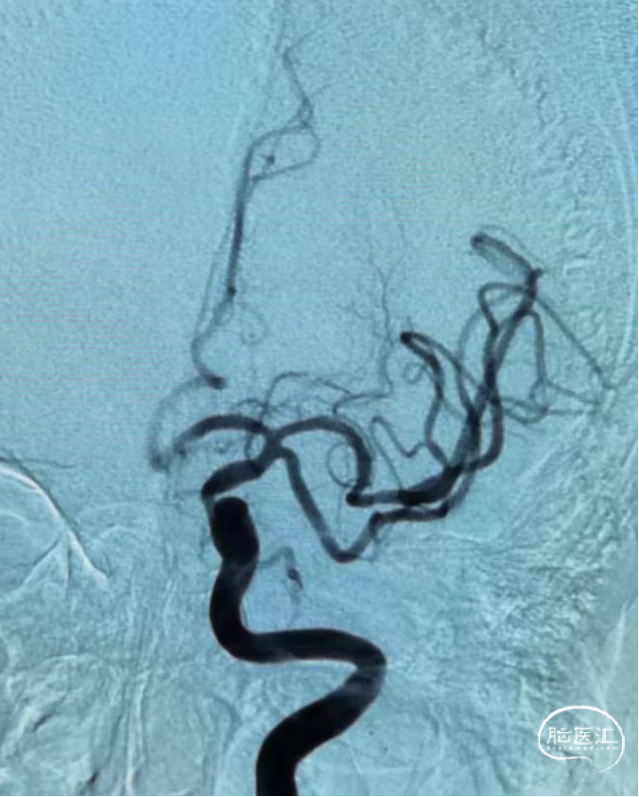

造影检查

左侧颈内动脉C6段闭塞